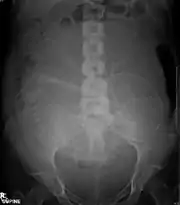

Abdominal radiograph of a pregnant woman, a procedure that should be performed only after proper assessment of benefit versus risk

Diagnostic X-rays (primarily from CT scans due to the large dose used) increase the risk of developmental problems and cancer in those exposed.[103][104][105] X-rays are classified as a carcinogen by both the World Health Organization's International Agency for Research on Cancer and the U.S. government.[96][106] It is estimated that 0.4% of current cancers in the United States are due to computed tomography (CT scans) performed in the past and that this may increase to as high as 1.5–2% with 2007 rates of CT usage.[107]

The risk of radiation is greater to a fetus, so in pregnant patients, the benefits of the investigation (X-ray) should be balanced with the potential hazards to the fetus.[117][118] In the US, there are an estimated 62 million CT scans performed annually, including more than 4 million on children.[111] Avoiding unnecessary X-rays (especially CT scans) reduces radiation dose and any associated cancer risk.[119]